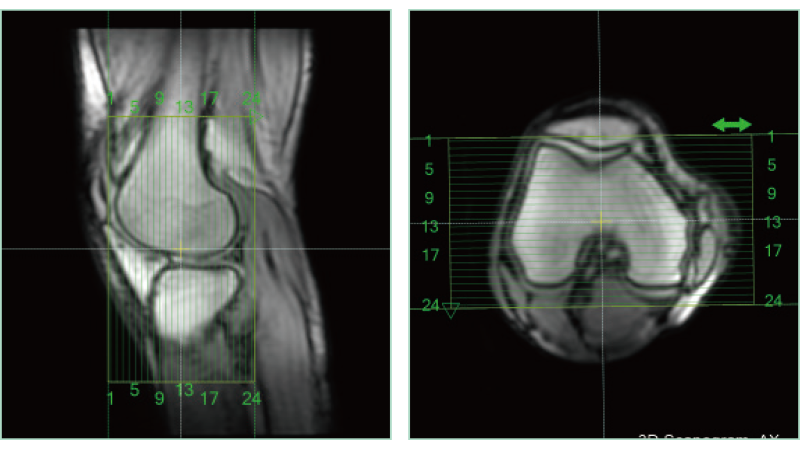

AutoPose Knee

A technology to convert extensive CT data accumulated through SYNAPSE 3D into MRI images utilizing AI technology has been developed. This technology, combined with a convolutional neural network (CNN) library established during the development of organ segmentation, has been utilized in the development of MRI positioning. As a result, highly accurate positioning capabilities have been commercialized for numerous anatomical regions.

The slice line setting support function, "AutoPose," automatically sets the slice lines as soon as the scanogram is scanned.